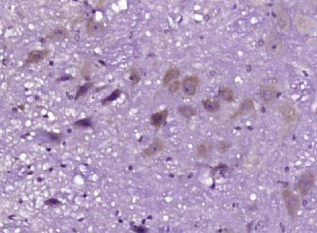

多聚甲醛固定,石蜡包埋(大鼠脑);用柠檬酸钠缓冲液(pH6.0)煮沸15min后获得抗原;用3%过氧化氢阻断内源过氧化物酶20分钟;阻断缓冲液(正常山羊血清)37℃30min;抗体(2 -调节蛋白)多克隆抗体在1:400下孵育。在4°C下,然后根据SP试剂盒(兔子)说明和DAB染色进行操作。